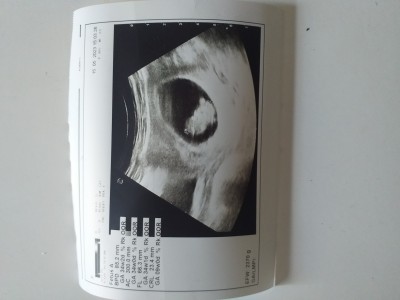

Mrb kızlar ben 9 haftalık hamileyim herkes öyle paylaşınca bende çok heves ettim hadi tahmin istiyorum bazıları sanki gerçekten biliyor keseye göre falan tahmin ediyorlar

Kese o kacaman siyah şey mi oluyor

Ewet canım yuvarlak olan varya bebeğinin dışında koruyan

Keseye göre kesin kız ama bebek hafif sola doğru bi şüpheye düştüm erkekte olabilir başka ultrason resmi varsa at bakalım bi daha